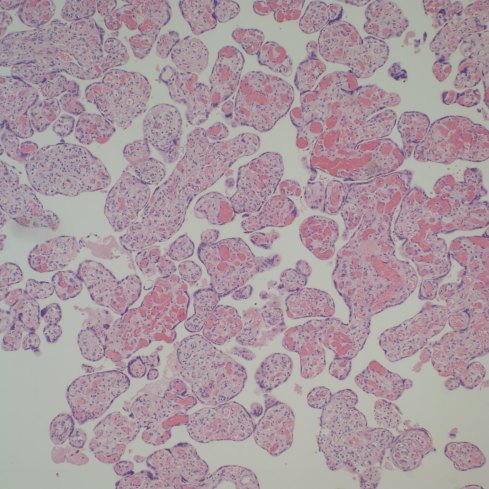

Distinguishing chorangiosis with its large terminal villi from persistent or increased intermediate villi is also not simple. I suspect that this confusion may be responsible for the association of maternal diabetes and chorangiosis. Dr. Ogino and Redline’s paper specifically mentions that the association is also with placentomegaly and delayed villous maturation. This problem can be seen clearly in looking at very early gestation placentas. (fig 2)